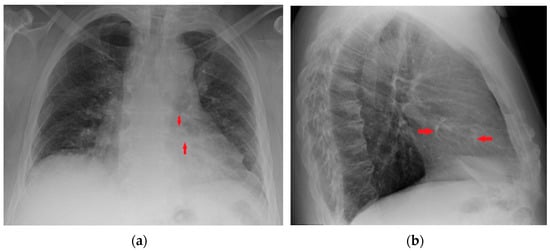

7. Chest Tubes